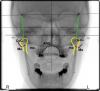

Skip Опубликовано 26 марта, 2010 Поделиться Опубликовано 26 марта, 2010 Правильно ли я нанёс ориентиры и видна ли связь проблемы и данных ТРГ?Ну что сказать, над ориентирами можно поработать немного, но для полноты картины не хватает ещё одной проекции, а именно submental vertex, а также анализ с Acculiner или другим артикулятором, да много ещё чего... Из предложенной инфомации, попробую начать с пациентки, страдающей головной болью, где наиболее интересен снимок во фронтальной области. Я внёс кое-какие поправки и теперь попытаемся проследить "связь проблемы". Первое, на что хотелось обратить внимание, так это положение височных костей. Чётко прослеживается их ротация, а именно справа вращение наружу (ER), слева - внуреннее вращение(IR).Девяносто пять процентов венозного дренажа мозгового черепа происходит посредством яремных вен, проходящих через очень уязвимое место в основании черепа а именно яремное отверстие. Сужение этого отверстия, в результате ротаций височной кости, может вызвать увеличение внутричерепного кровяного давления, которое может быть источником головных болей. Как правило, эти головные боли ощущаются, как давление вдоль вершины головы, то есть в области стреловидного шва. Но, это лишь одна из ряда причин, о которых сейчас нет времени рассказать, уже убегаю на работу... Взаимная пространственная ориентация височных костей по отношению друг к другу и к смежным костям очень важны в методе A.L.F., как диагноза, так и лечения. Височные кости находятся в непосредственной связи с затылочной костью, которая оказывает своё влияние на них. Затылочная кость - главное посредник между ВНЧС- комплексом и шейным отделом позвоночника. Височные кости, как считают остеопаты, являются гомологами подвздошных костей таза. Это означает, что, если височные кости не на одном уровне относительно друг друга, то может возникнуть соответствующая неустойчивость таза и наоборот. Эти отношения между височными костями и тазом должны быть обязательно признаны. Нижняя челюсть переместится к внешне вращаемой стороне (ER) височной кости, так как суставная ямка на этой стороне раcположена более дистально. Важность височных костей, для стоматолога, состоит не только для оценки положения суставных ямок и положения нижней челюсти. Есть девять из двенадцати черепномозговых нервов, проходящих через височную кость или в непосредственной близости к ней. Смещение пирамиды височной кости может не только затронуть органы слуха и вестибулярный аппарат, но также может вызвать неврологические нарушения, связанные с любым из нервов, выходящих через эту кость или находящихся непосредственно вблизи. Есть множество сообщений в остеопатической литературе, об эффективном лечении невралгии тройничного нерва, посредством черепной манипуляции. Ссылка на комментарий

Skip Опубликовано 27 марта, 2010 Поделиться Опубликовано 27 марта, 2010 Обратите внимание на соотношение орбитальной (Eyes), ушной (Ears) и верхнечелюстной (Maxilla) плоскостей. Ушная и верхнечелюстная совпадают по направлению, а орбитальная нет. Согласно анализу Walker (Tri-Planar), это говорит об очень ранней черепной компенсации (до 12 лет) или как результат стоматологического лечения (я так думаю, что те штампованные мосты и коронки + перекрёстный прикус) Ссылка на комментарий